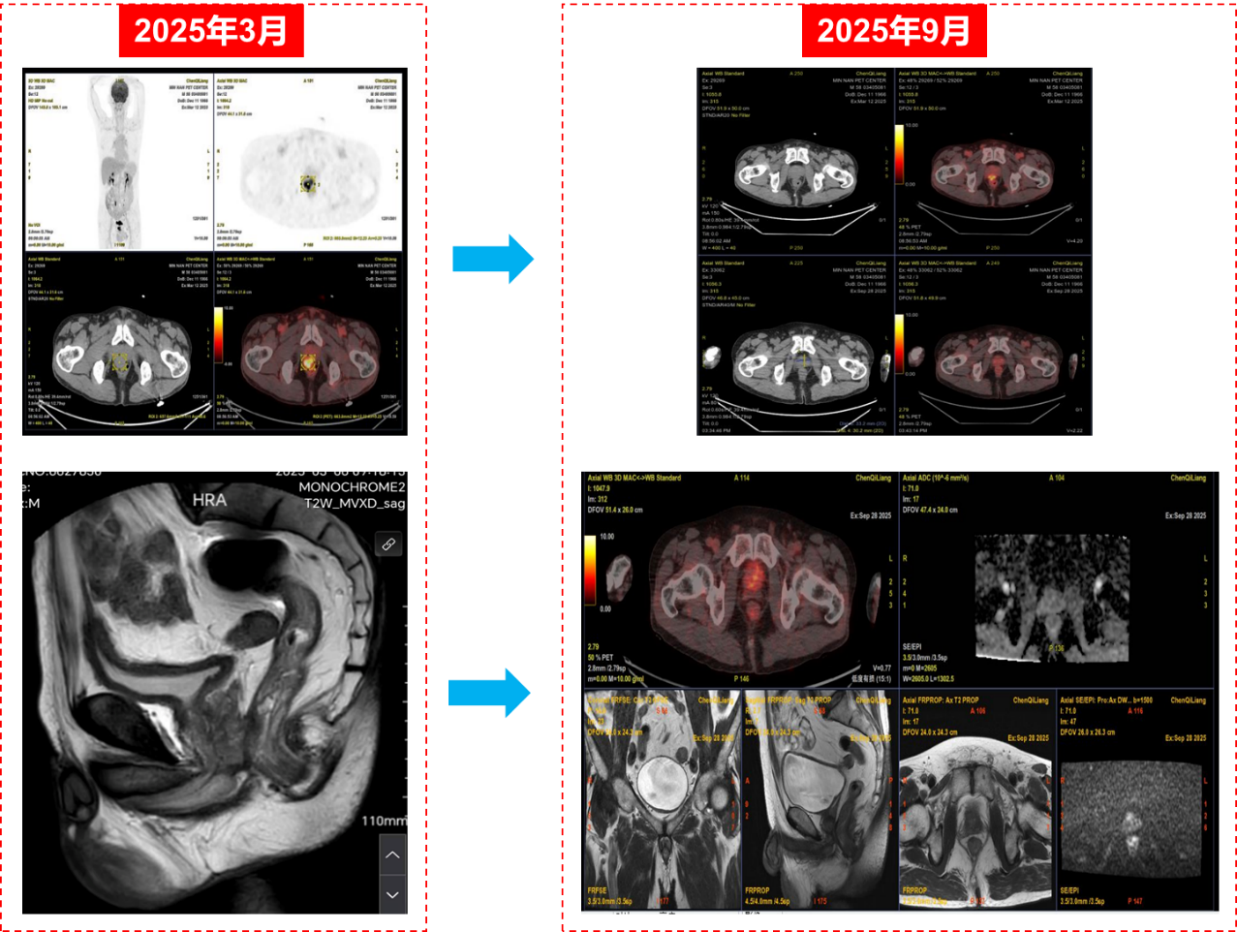

根据SEGNO研究预设方案,患者接受NHA + ADT + PARP抑制剂的新辅助三联治疗,具体用药为:瑞维鲁胺 240 mg 口服 每日一次+戈舍瑞林缓释微球 3.6 mg 肌内注射,每 4 周一次+帕米帕利 60 mg 口服 每日两次。整个新辅助治疗历时约6个月,期间患者总体耐受性良好,未出现剂量限制性毒性。随访过程中PSA水平迅速下降并维持在不可测水平(图3);新辅助治疗结束时复查PSMA PET/CT未见前列腺原发灶、盆腔淋巴结及远处骨骼异常摄取灶,与基线相比病灶代谢信号基本消失,影像学评估达到临床完全缓解(cCR)(图4)。

新辅助治疗结束并经术前评估确认具备手术条件后,患者接受机器人辅助根治性前列腺切除术联合盆腔淋巴结清扫。术中未观察到显著治疗相关纤维化黏连或广泛肿瘤浸润,手术顺利完成,术后恢复平稳。术后病理检查显示前列腺标本内仅残留极少量散在癌细胞,瘤床肿瘤细胞减少>90%,肿瘤负荷较基线显著下降,切缘阴性,盆腔淋巴结未见癌转移,病理学评估显示达到病理最小残留病灶(pMRD),并接近病理完全缓解(pCR)。综合术前cT4N1M0分期、BRCA2/HRR通路致病性改变这一高风险生物学背景及新辅助后PSMA PET/CT评估为cCR的结果,本例呈现影像学与病理学一致的深度缓解(pMRD,近pCR)。该个案提示在BRCA2/HRR缺陷亚组中,PARP抑制剂参与的分层三联新辅助策略可获得早期深度肿瘤学缓解,并可能预示更有利的长期结局,尚需进一步随访数据加以验证。同时,本病例亦为SEGNO研究所采用的基因分层新辅助治疗路径提供了临床层面的支持性证据。